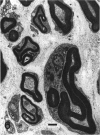

The morphological changes were examined proximal and distal to crush and transection injuries of the lingual/chorda tympani nerve. Under general anaesthesia the nerve was transected unilaterally in 6 adult cats and crushed with watchmakers forceps in 6 others. After 12 wk, again under general anaesthesia, the injured and contralateral (control) nerves were removed, fixed and embedded for histological examination. Sections were cut from sites proximal and distal to the injury and from a site equivalent to that of the injury on the control side. Using systematic randomised sampling techniques the number of nonmyelinated axons and the number and size of myelinated axons in each nerve at each location was estimated. In addition, the mean number of nonmyelinated axons in each Schwann cell unit was determined. The only significant difference between control and injured nerves proximal to either injury was a reduction in the number of myelinated axons in the chorda tympani after transection, and an increase in their mean size. This indicates a selective loss of smaller fibres and is consistent with the poor recovery of gustatory and thermosensitive fibres previously reported (Robinson, 1989). Distal to both types of injury there was an increase in the number of fascicles. The mean number of myelinated axons was reduced distal to a crush injury but unchanged distal to transection. The number of nonmyelinated axons distal to a transection injury was 5 times control counts and after a crush injury double. These findings suggest that sprouting persists 12 wk after both injuries but is much greater after transection.